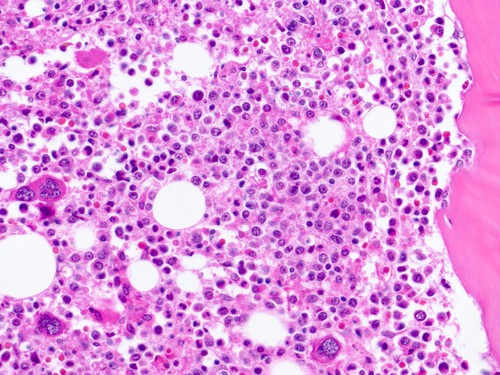

Quá trình xét nghiệm tủy xương: Người bệnh sẽ được tiến hành sinh thiết tủy, phân tích sinh khối máu và tế bào tủy xương giúp xác định, chẩn đoán và tiên lượng bệnh.